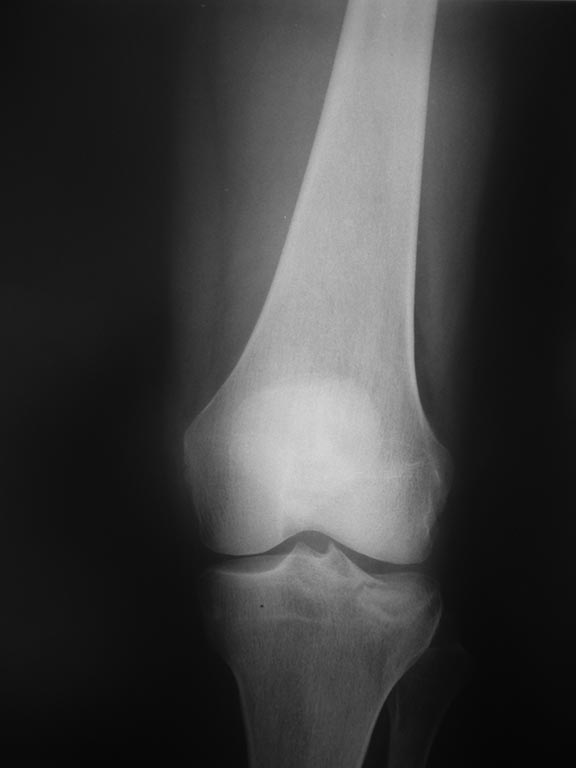

Re: Импрессионный перелом латерального мыщелка левой большеберцевой кости.

Учитывая, что у пациента молодой возраст(судя по рентгенограммам,абсолютно показано восстановление суставной линии: подменисковый доступ,подъём импренированной части мыщелка, костная аутопластика, остеосинтез, решение вопроса с мениском (шов либо парциальная резекция)).